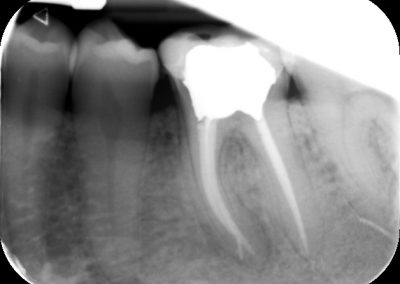

Files of different sizes are used to eliminate bacteria and infection and to shape the canals. The canals are disinfected thoroughly with irrigants and later the canals will be sealed in 3 dimensions with a special medicament called gutta-percha to prevent reinfection of the tooth and the access cavity will be sealed with a temporary filling.

How is the tooth protected after the root canal treatment?

After a few weeks, the tooth will be checked and when all the infection has cleared, a crown will be usually required to protect the restore the tooth to function.